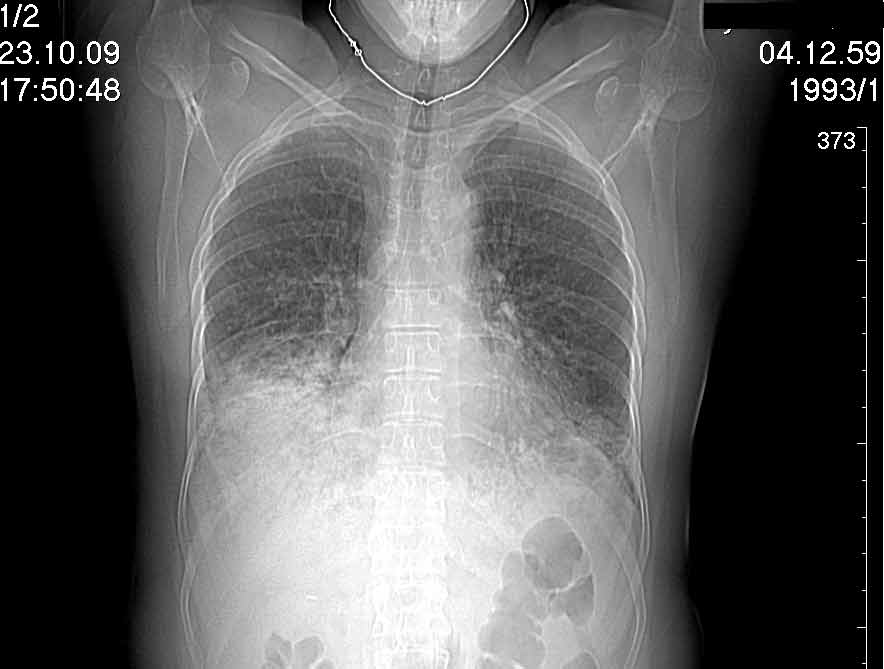

Случай №3

Женщина 51 год

Случай 3:смешанные изменения; подходят для интерстициальной пневмонии, тактика аналогична случаю 1.